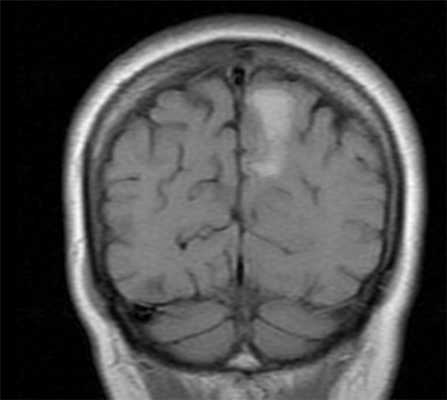

МРТ головного мозга. Т1-взвешенная корональная МРТ. Смешанный ишемический инсульт. Ранняя подострая стадия.

В подострой стадии кровоизлияния гемоглобин редуцируется до метгемоглобина, который обладает выраженным парамагнитным эффектом. В раннюю подострую стадию (3 - 7 сутки) метгемоглобин располагается внутриклеточно и характеризуется коротким временем релаксации Т2. Это проявляется низким сигналом на Т2-ВИ и гиперинтенсивным на Т1-ВИ. В позднем периоде подострой стадии (1 - 2-я неделя) продолжающийся гемолиз приводит к высвобождению из клеток метгемоглобина. Свободный метгемоглобин имеет короткое время релаксации Т1 и длинное Т2 и, следовательно, обладает гиперинтенсивным сигналом на Т1-ВИ и Т2-ВИ и FLAIR.